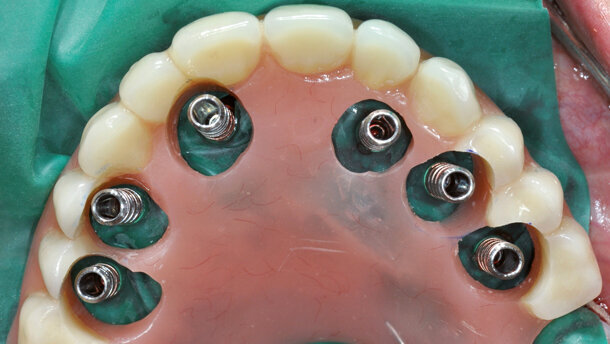

Gli impianti sono stati inseriti con un torque di 25 Ncm, usando un contrangolo e la Implant Driver EV (Fig. 4). L’installazione finale è stata eseguita manualmente. Successivamente gli abutments Uni EV da 2 mm sono stati collegati manualmente agli impianti utilizzando l’Uni Driver EV (Fig. 5).

I cilindri provvisori Uni Abutment EV sono stati collocati sui monconi per fissare la protesi provvisoria. La procedura chirurgica è stata completata con il riposizionamento dei lembi di tessuto molle e la sutura attorno ai monconi (Fig. 6).